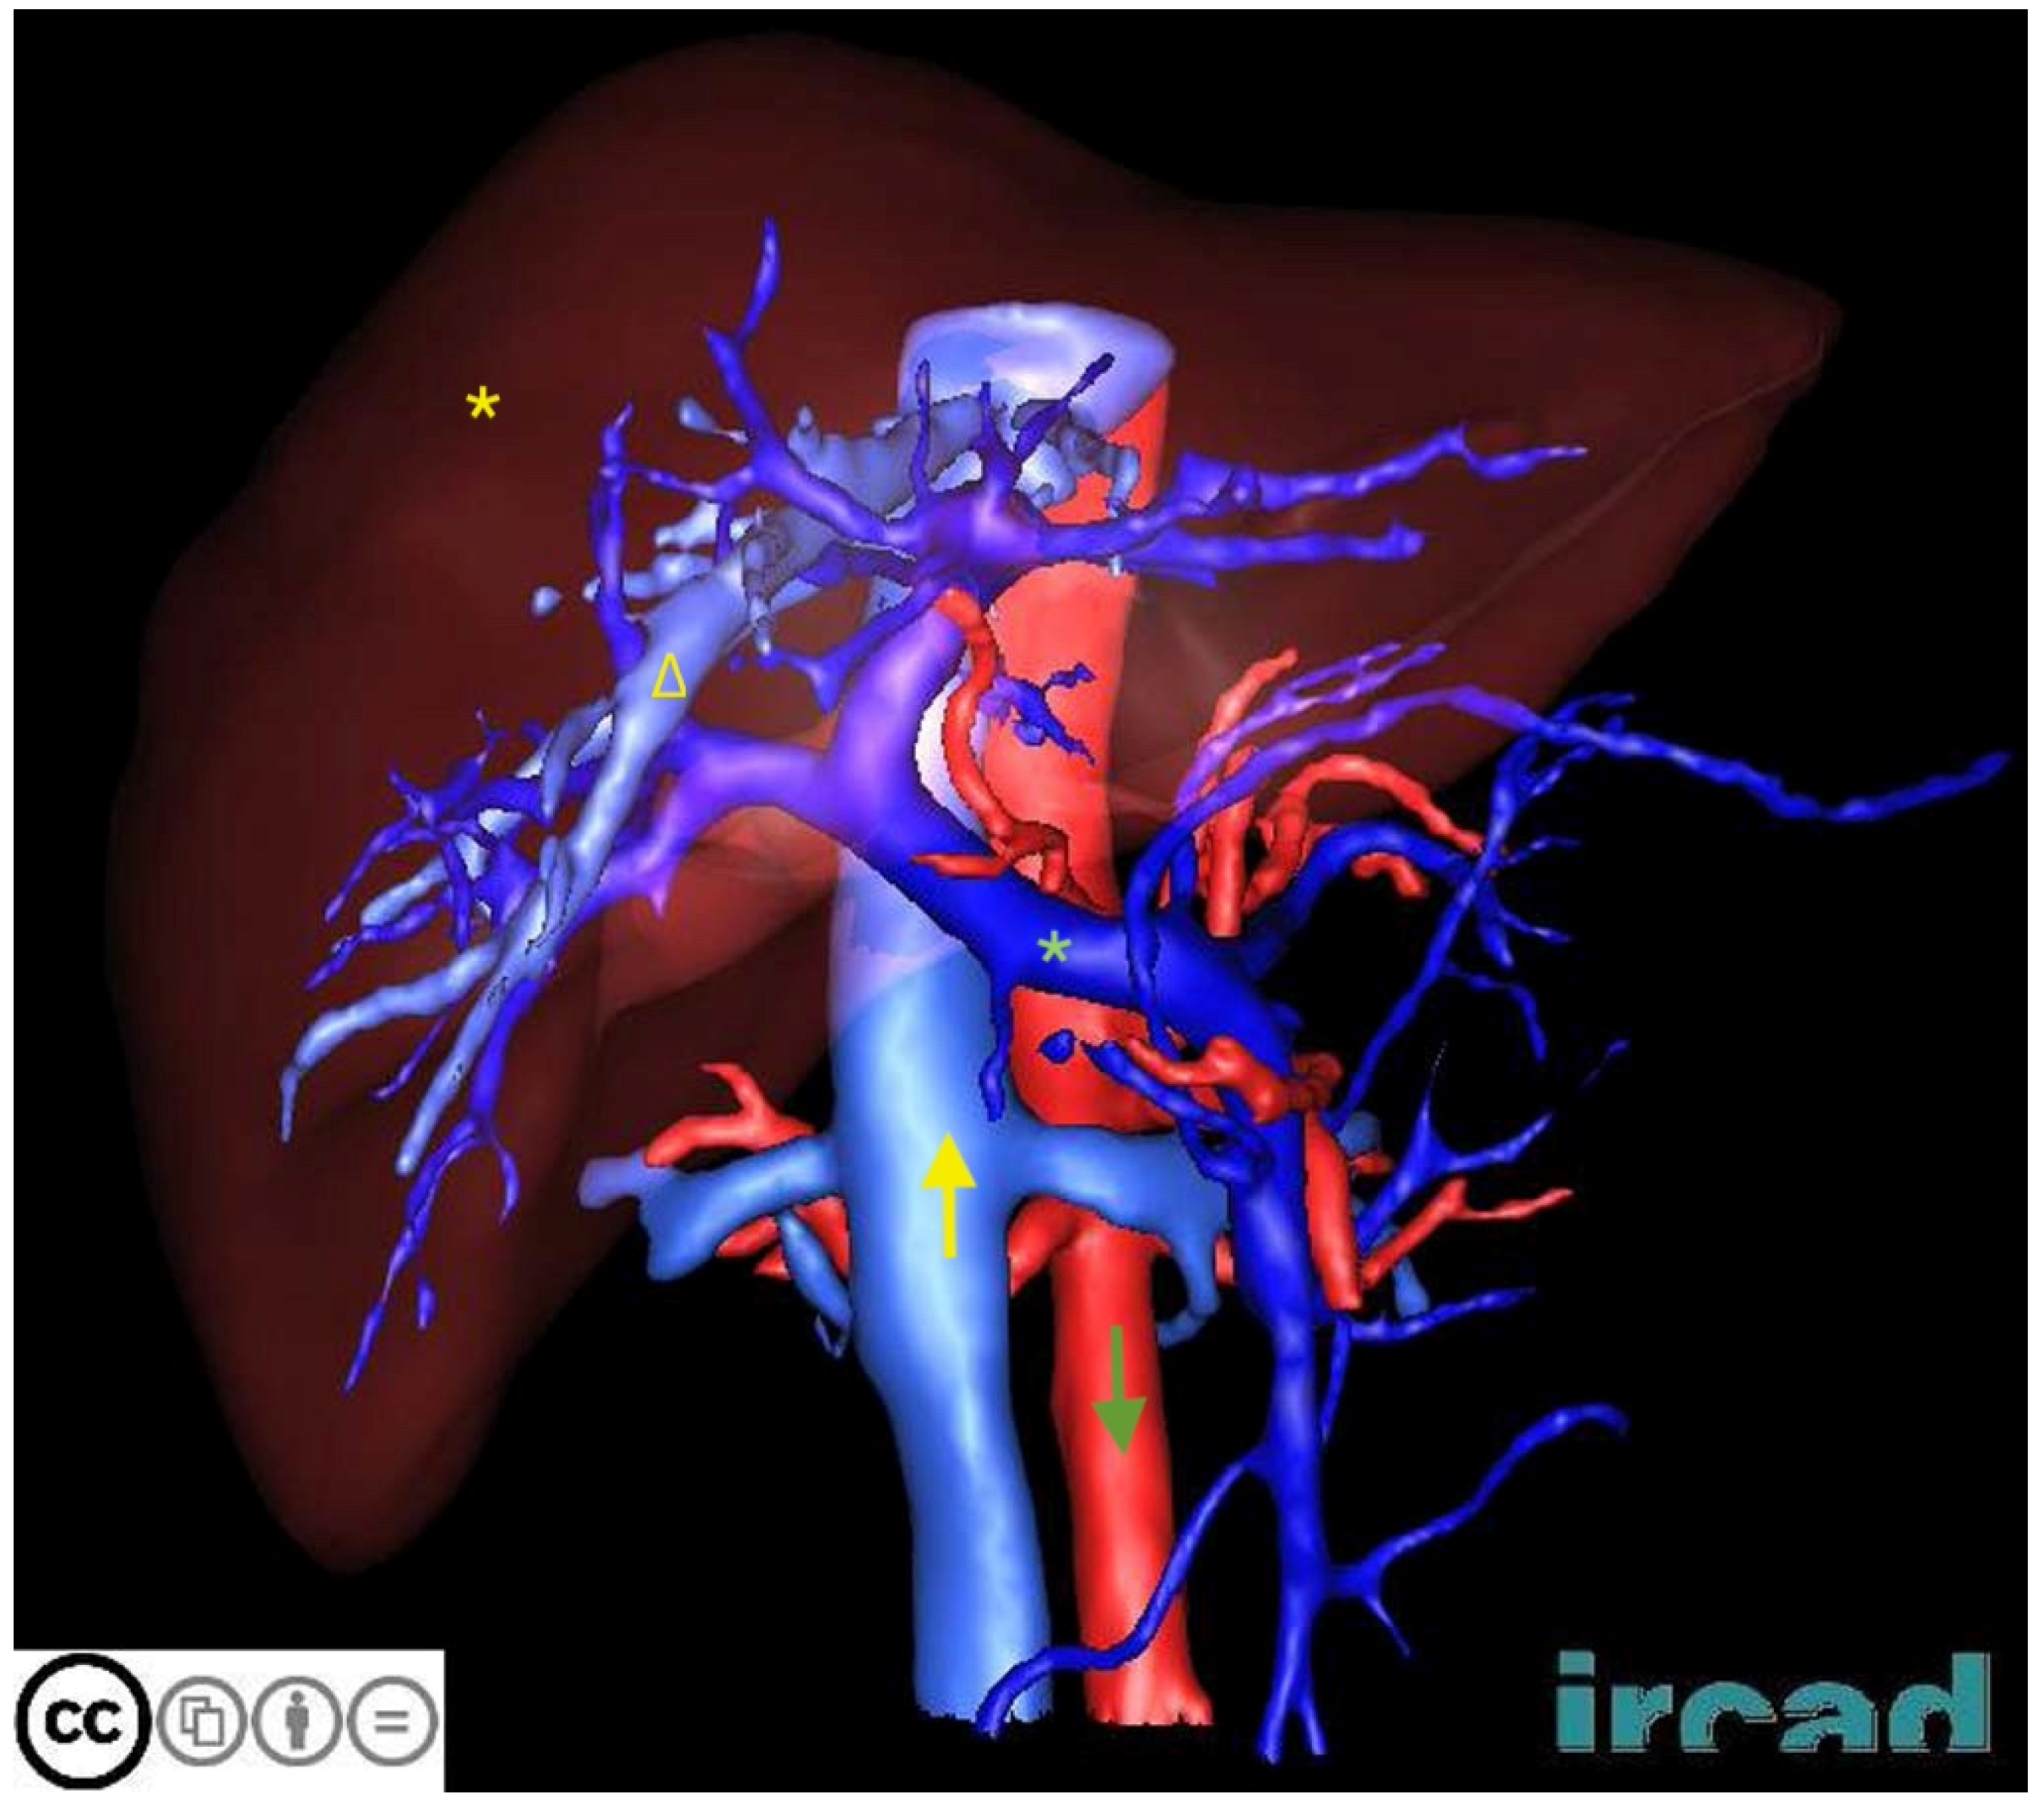

| 3DIRCADb | CT scans from 20 patients with annotations for liver and liver tumor segmentation | Detailed 3D reconstruction data aid the development of segmentation algorithms for complex liver structures | Small sample with limited case types |